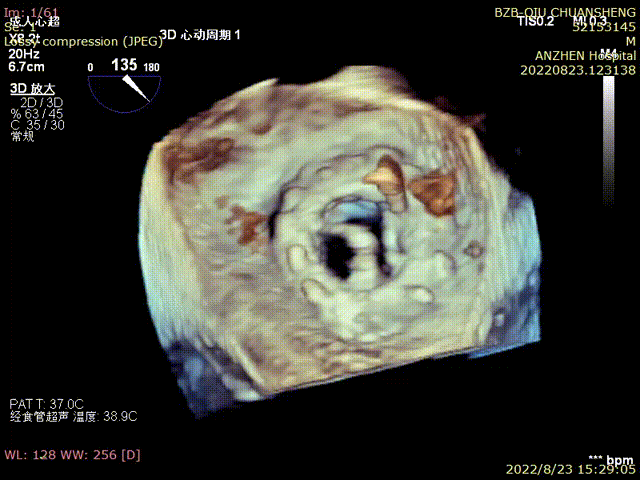

TEE-TMVIV-3D-撤出介入器